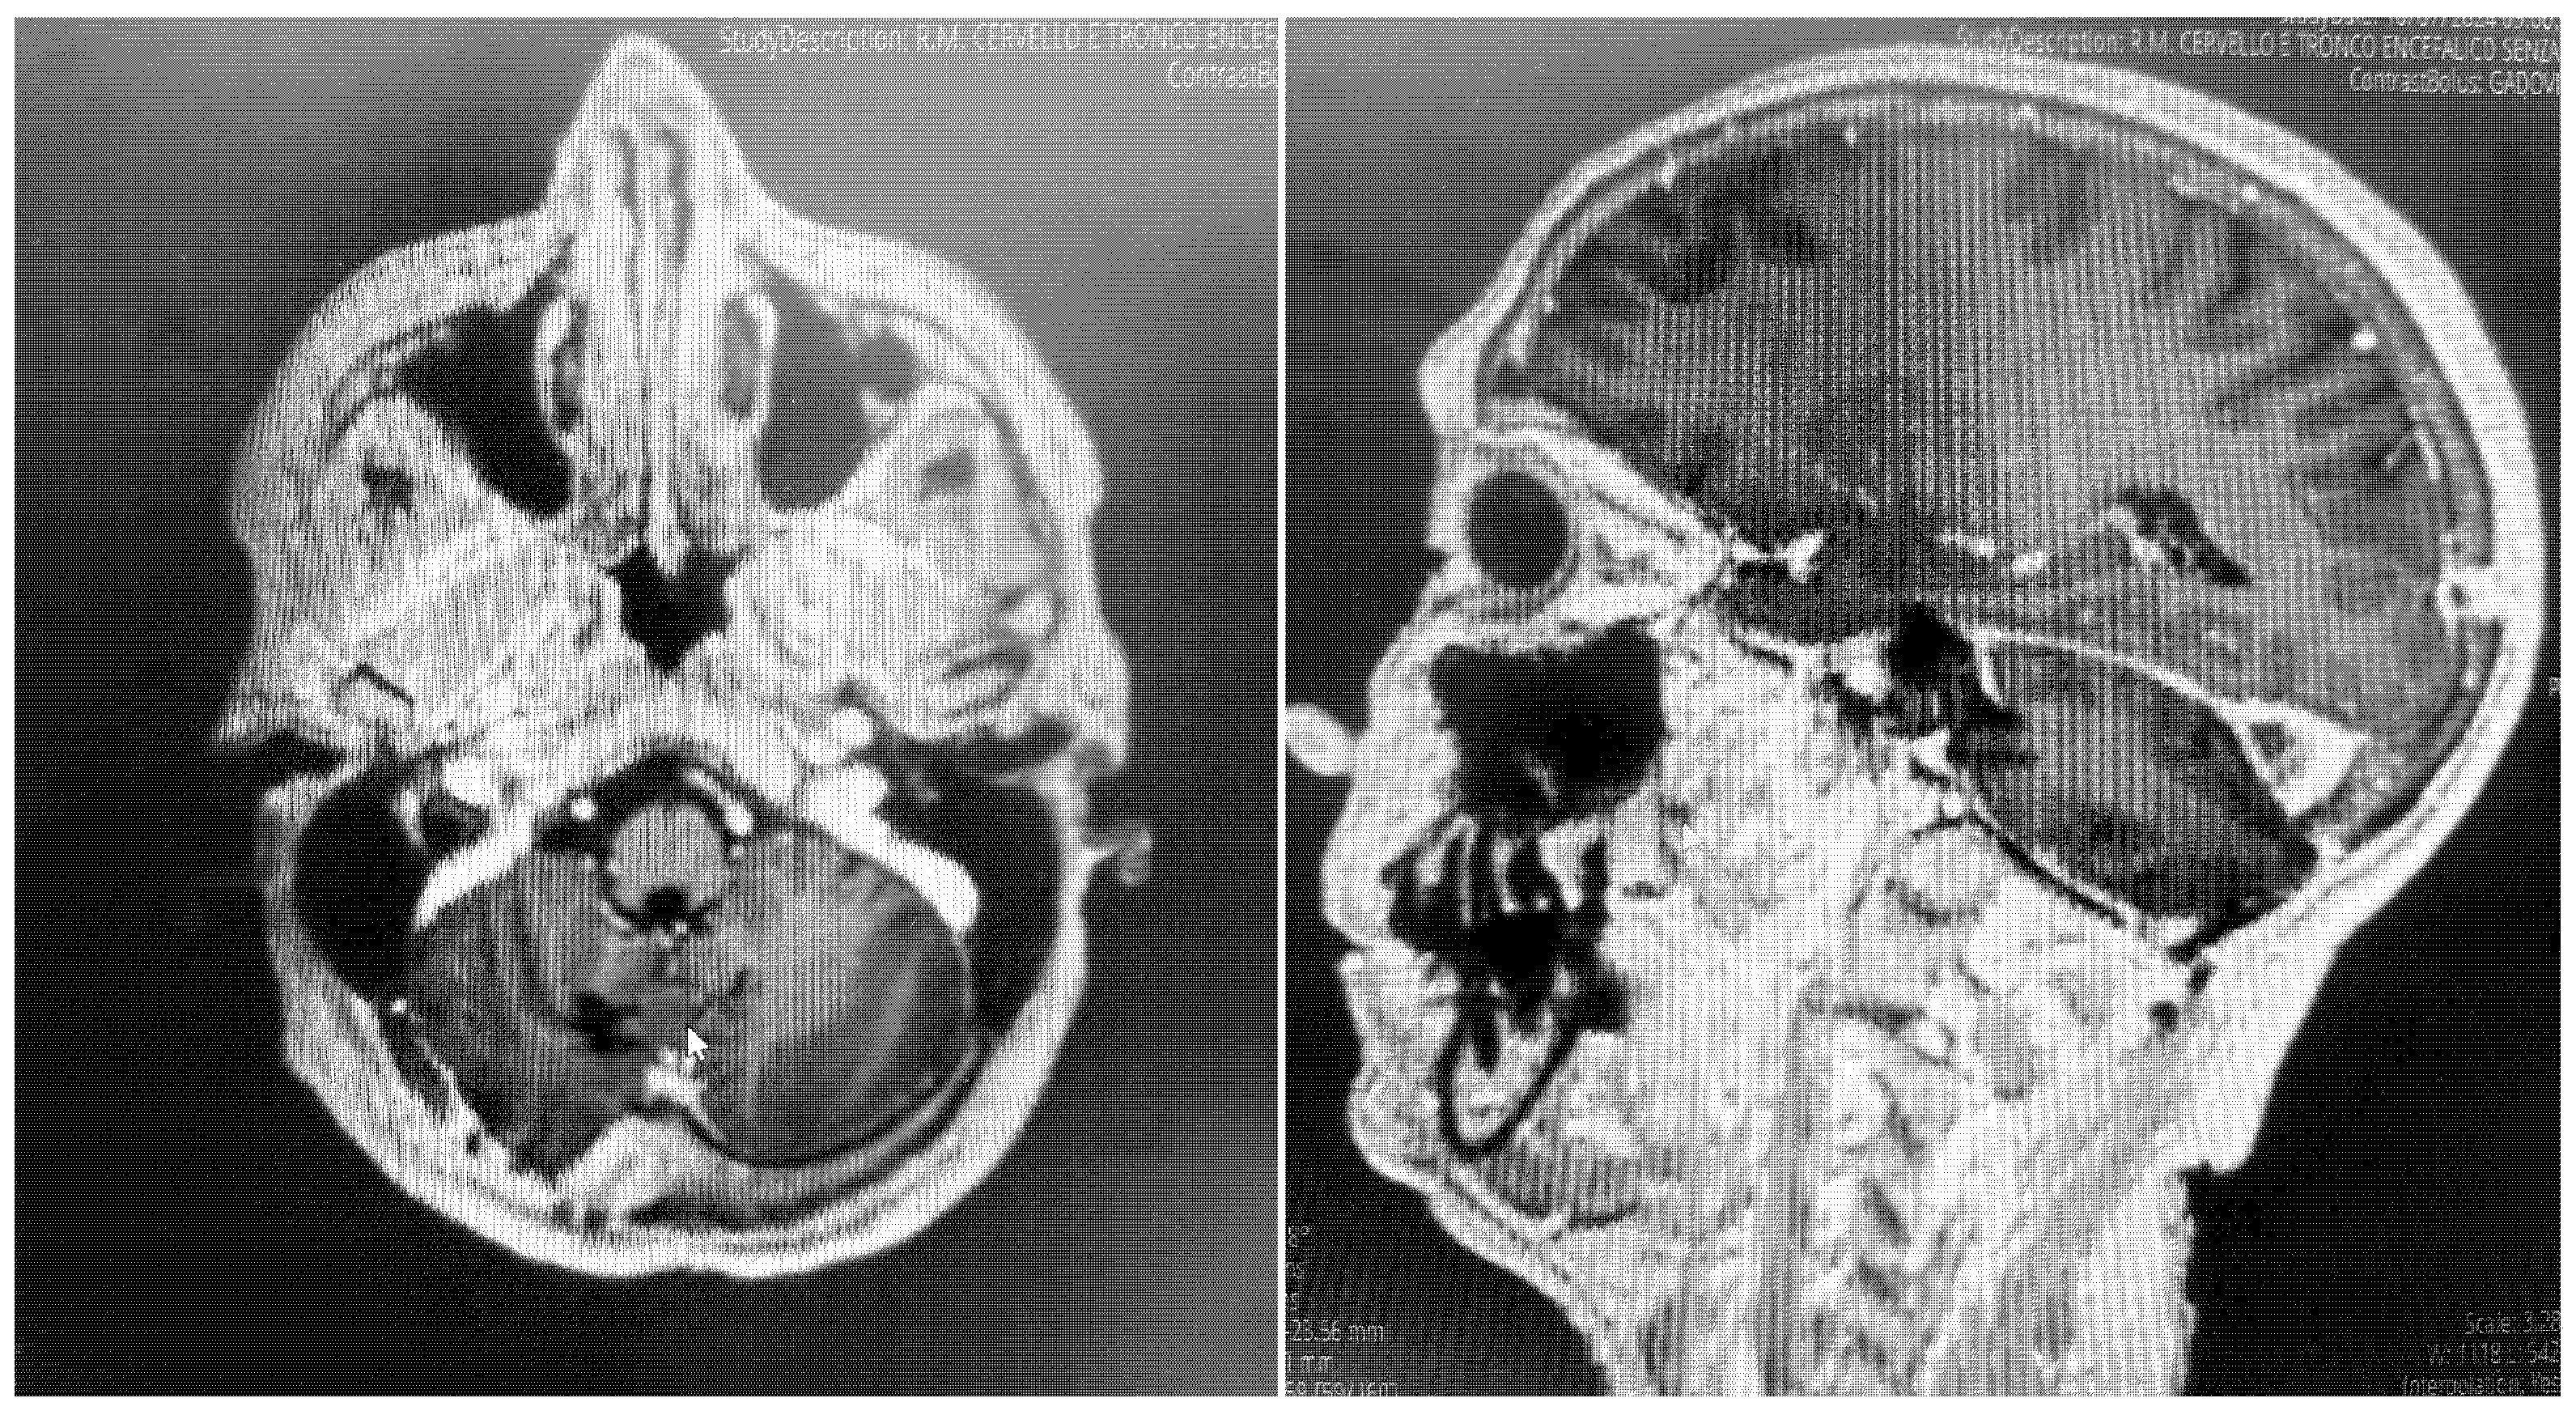

To strengthen the oncologic perspective, we added an 18-month contrast-enhanced MRI, demonstrating no residual or enhancing recurrence (Figure 5). While early postoperative findings were favorable, meningiomas require longer-term surveillance. Our current imaging aligns with standard practice and supports durable tumor control at 1 year. Continued surveillance will follow institutional protocol, with annual MRI for at least 5 years, tailored to WHO grade, Simpson resection grade, and histopathology.

Figure 5. Post-contrast T1-weighted MRI at 18 months following resection. Axial and sagittal images at the level of the prior tumor demonstrate no nodular or mass-like enhancement to suggest residual or recurrent meningioma.